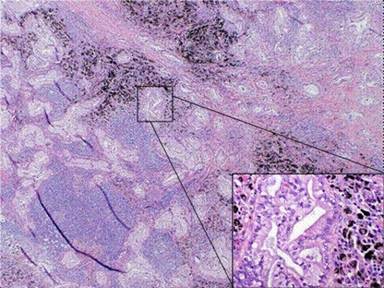

Additional staging evaluations for presumed recurrent thyroid cancer included a CT chest/abdomen, and a mass suspicious for pancreatic cancer was incidentally identified in the pancreatic tail. A CA 19-9 was obtained and found to be 1,099 U/mL. Given the high likelihood of the pancreatic mass representing a separate primary, the patient underwent subtotal pancreatectomy and splenectomy. The mass was confirmed to be a 3.5 cm ductal-type adenocarcinoma invading the peripancreatic adipose tissue with lymphatic vascular invasion, negative nodes and clear margins. The initial staging for pancreatic cancer appeared to be pT3pN0M0 with resected stage IIA disease (Table 1). The patient was scheduled to initiate adjuvant chemotherapy with single agent gemcitabine. However, prior to initiation of adjuvant therapy, excisional biopsy of the left supraclavicular nodes showed metastatic mucinous adenocarcinoma characteristic of metastatic pancreatic adenocarcinoma (Figure 4). PET/CT scan also showed focal areas of increased uptake in the left supraclavicular region. No other sites of metastatic disease were identified on CT scan or PET/CT scan.

Figure 4. Microphotograph of a left supraclavicular lymph node of Patient #3. Malignant glands (magnified in inset 200x) are present in lymphoid tissue with anthracotic pigment (50x magnification; hematoxylin & eosin stain). |